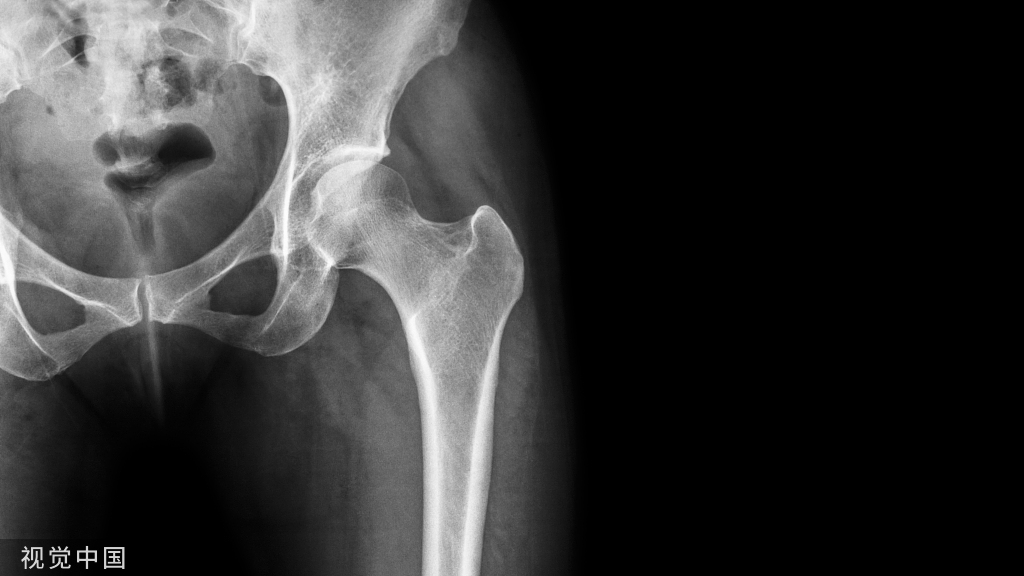

Calve线

卡尔维氏线,即髂颈线。髋关节正位片上,髂前下棘下方髂骨外缘与股骨颈外缘连线所形成的弧线,能够反映股骨头与髋臼的关系及髋臼上缘的完整性。正常为光滑曲线,若不连续提示髋关节脱位或者股骨颈错位骨折。

Shenton线

又叫沈通氏线、耻颈线、下弧线,是指成人髋关节正位片上,闭孔上缘与股骨颈内下缘连线,能够反映股骨头与髋臼的关系。正常应为平滑曲线,若不连续提示髋关节脱位或者股骨颈错位骨折。